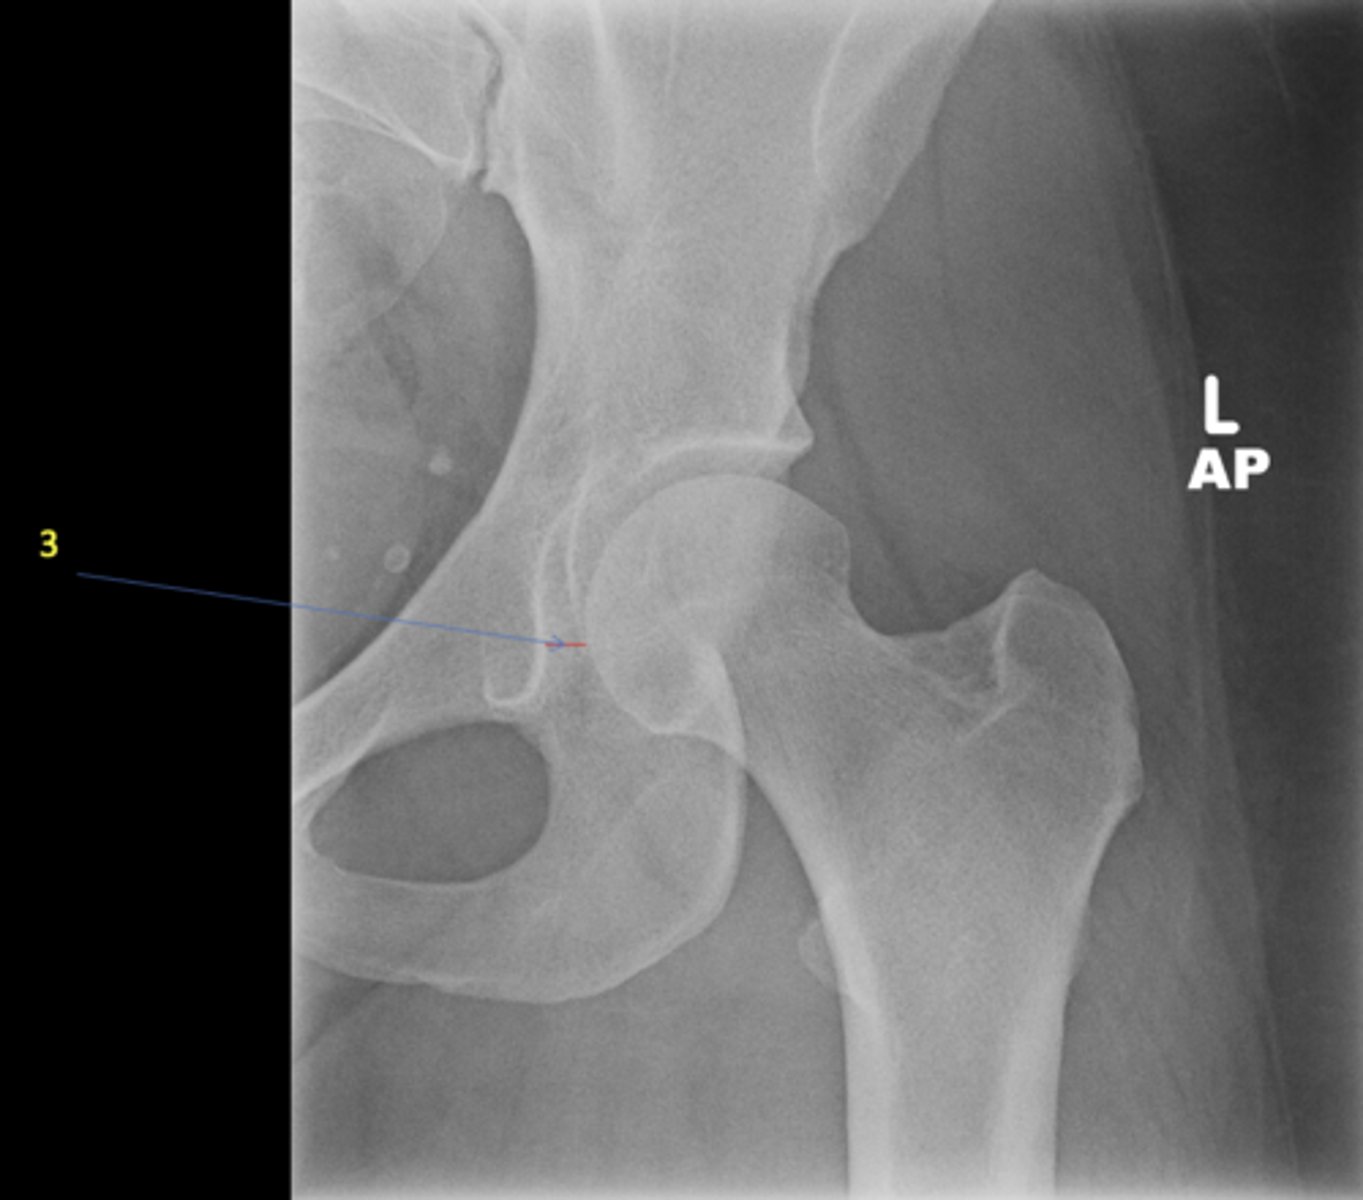

3

New cards

Left greater trochanter

ID 3

<p>ID 3</p>